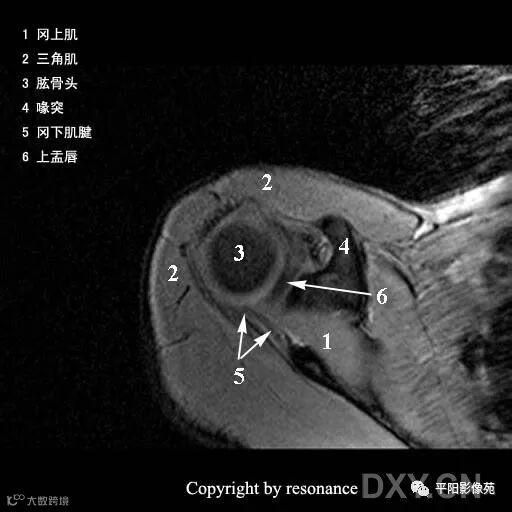

解剖

冈上肌肌腱:斜冠位、轴位显示最佳

止点位于肱骨大结节的上外侧面

冈下肌肌腱:轴位显示佳

止点位于肱骨大结节的后下方

小圆肌肌腱:轴位显示佳

指点位于肱骨大结节更下方,冈下肌肌腱下方

肩胛下肌肌腱:轴位和斜矢状位显示佳

止点位于肱骨小结节的前部